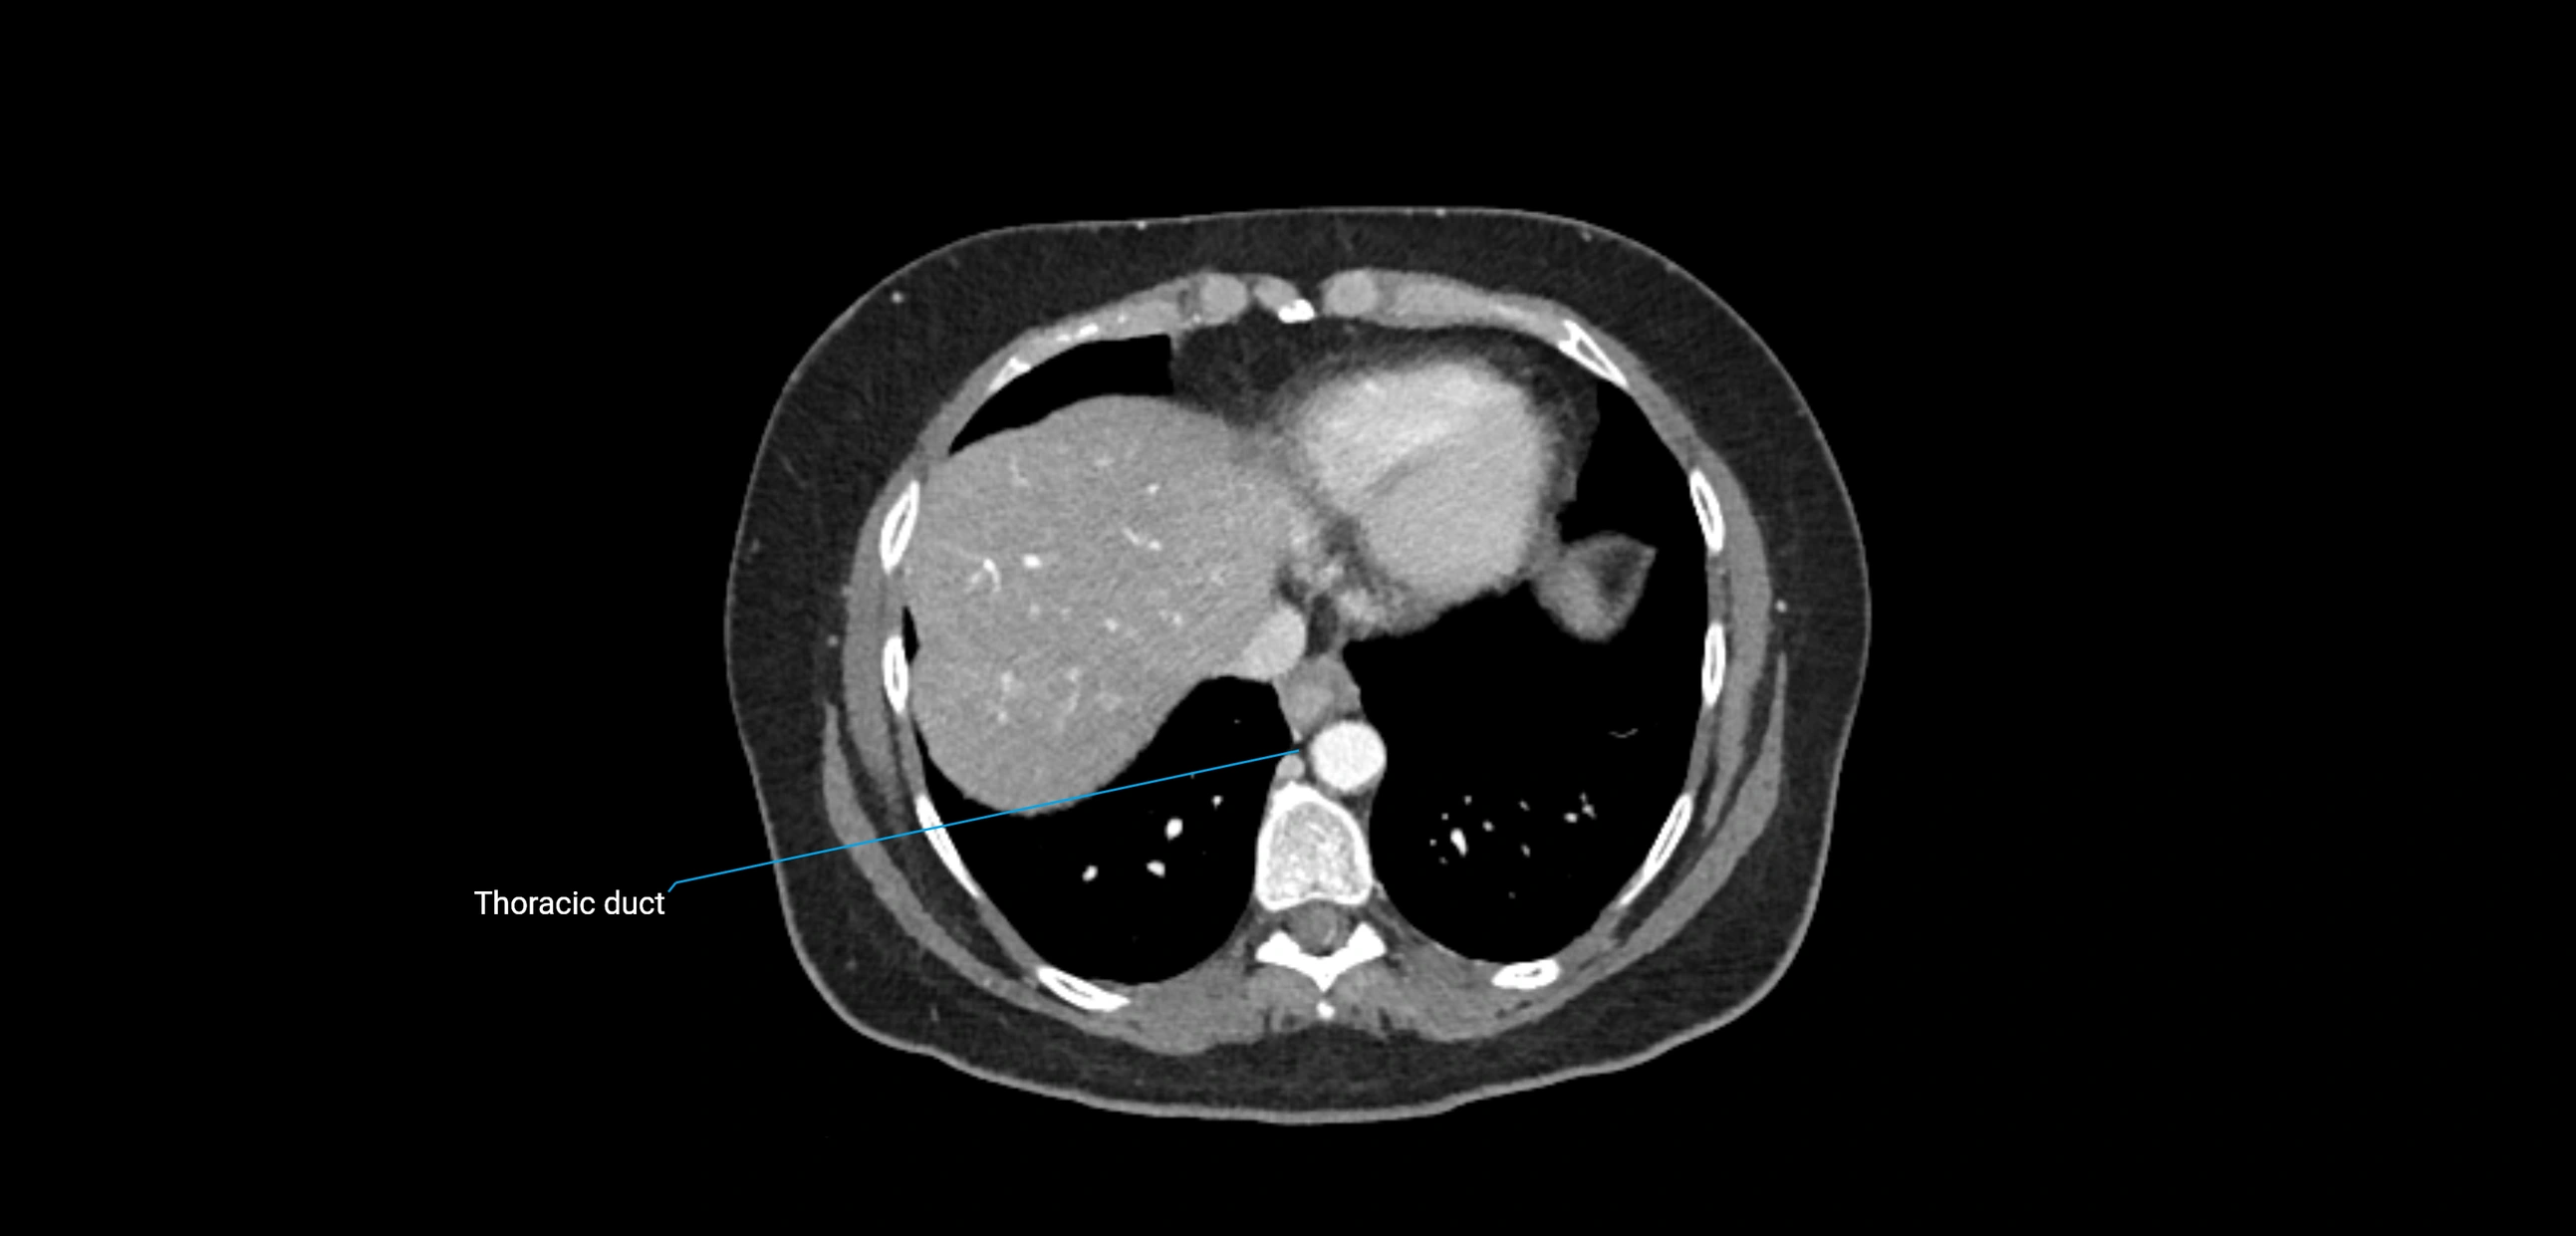

These nodes receive lymph from a wide range of abdominal and pelvic structures. Specifically, they drain lymph from the kidneys, suprarenal glands, gonads (testes/ovaries), uterus, uterine tubes, and pelvic organs, before converging into the lumbar lymphatic trunks, which terminate in the cisterna chyli → thoracic duct.

• Provide a major pathway to the cisterna chyli and thoracic duct

CT Appearance

CT Post-Contrast:

• Normal nodes enhance homogeneously

• Malignant nodes may show heterogeneous enhancement, central necrosis, or conglomerate formation

CT Venography (CTV):

• Demonstrates nodal encasement or compression of adjacent vessels (aorta, IVC, renal veins)

• Useful in staging testicular and ovarian malignancies

• Provides 3D reconstructions for retroperitoneal lymph node dissection planning